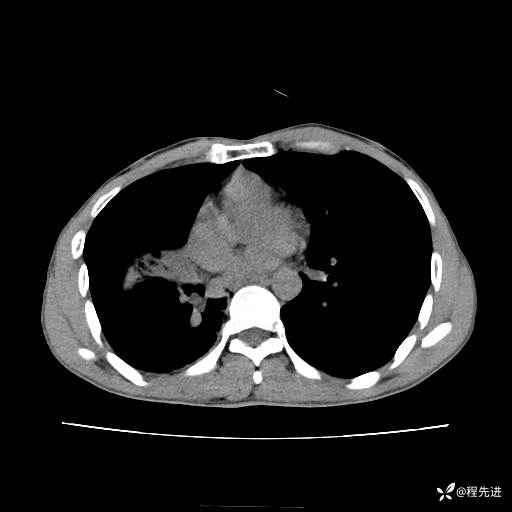

患者性别:男

患者年龄:49岁

主诉:咳嗽、胸痛1周

简要病史:1周前受凉感冒后开始出现咳嗽症状,阵发性连声咳,痰多,黄白痰,不易咳出,伴胸痛、气紧、胸闷,右侧为主,活动用力、呼吸时胸痛明显,曾在当地诊所贴敷膏药仍疼痛

体格检查:T:36.3 ℃ P:80 次/分 R:20 次/分 BP:120/88 mmHg,指脉氧饱和度97%,意识清晰,呼吸平稳,右侧第二、三肋骨压痛,可见膏药贴敷,皮肤无异常,双肺呼吸音粗,未闻及干湿性啰音。心率80次/分,节律整齐,无杂音。腹平软,全腹无压痛无反跳痛

临床诊断:社区获得性肺炎

CT平扫: